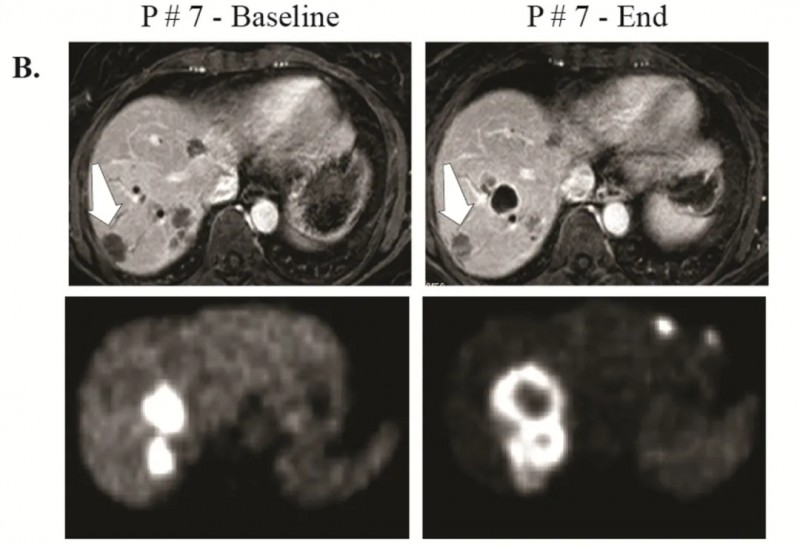

7号患者:呈现部分应答,部分病灶缩小、代谢减低,其背部病灶在MRI上可见缩小,PET检查中未显示(详见下图B)。

▲图源“Clin Cancer Res”,版权归原作者所有,如无意中侵犯了知识产权,请联系我们删除